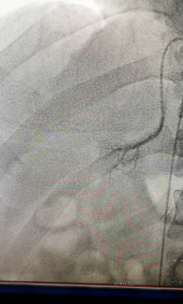

——我院成功开展双侧肾上腺静脉插管采血术 近日,我院心内科、检验科、内分泌科、泌尿外科多科协作,成功开展了双侧肾上腺静脉插管采血术。该项高血压诊疗新技术目前只在国内少部分医院开展。我院首次开展此项技术后,明确了患者高血压的病因,实现了高血压的精准治疗,标志着该院对高血压的诊治水平提高到了一个新的台...